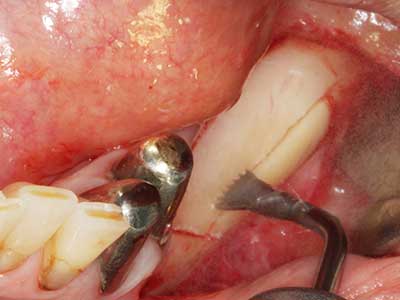

Si es preciso realizar intervenciones quirúrgicas en las que el hueso está en contacto directo con estructuras sensibles, como son los vasos sanguíneos o los nervios, los instrumentos rotativos presentan un enorme potencial de provocar lesiones iatrogénicas. Así, precisamente en la representación de nervios después de una lesión iatrogénica, o en el transcurso de la lateralización de un nervio para resecciones, reconstrucciones o incorporación de implantes, los equipos piezoeléctricos pueden resultar muy útiles para preparar la tapa ósea y retirar las partes de tejido duro cercanas al nervio (fig. 17-20). Por lo general, un ligero contacto del cordón nervioso con el inserto piezoeléctrico no tiene consecuencia alguna; ahora bien, un procedimiento poco cuidadoso con movimientos tipo sierra o piezas de trabajo sobre la base ósea aún existente puede provocar lesiones nerviosas temporales o incluso permanentes. Con todo, el riesgo de sufrir una lesión de este tipo se considera significativamente inferior que en los casos en los que se utilizan sierras y fresas (Pereira, Gealh et al. 2014).

Fig. 17: Tomografía computarizada de un osteoma de crecimiento progresivo ...

Fig. 17b: justo al lado del canal alveolar con irritación nerviosa (vista lateral y coronal).

Fig. 18: Preparación de una tapa cortical con la sierra ósea piezoeléctrica (Piezomed, W&H).

Fig. 19: Zona operada después de neurolisis y eliminación del osteomo.

Fig. 20: La tapa ósea extraída se readapta y se fija mediante un tornillo para osteosíntesis (KLS Martin, Tuttlingen).